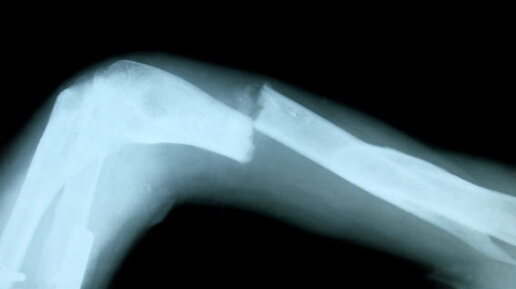

Как узнать, сломана ли кость?

Кости могут сломаться после несчастного случая, например, падения или удара каким- либо предметом. 3 наиболее распространенных признака перелома кости (также известного как перелом): Однако иногда бывает трудно определить, сломана ли кость, если она находится не в своем нормальном положении. Если сломана кость: Вы также можете почувствовать слабость, головокружение или тошноту в результате шока от перелома кости. Если перелом небольшой или это просто трещина, вы можете не почувствовать сильной боли или даже осознать, что сломали кость...

Как понять, что у меня перелом? Ортопед о главных и скрытых признаках

Здравствуйте, уважаемые читатели! С вами доктор Тимофей Скипенко, врач-ортопед-травматолог. В практике каждого моего рабочего дня есть один и тот же диалог: пациент, осторожно придерживая руку или прихрамывая, спрашивает: «Доктор, скажите честно, это перелом или просто ушиб?». Вопрос жизненно важный, ведь от ответа зависит тактика лечения и ваше быстрое восстановление. Сегодня я хочу стать вашим проводником и подробно, на пальцах, объяснить, как отличить серьезную травму от неопасной. Запомните: ваша бдительность может предотвратить тяжелые осложнения...